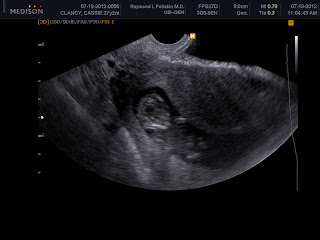

Wahooooooo! I had another ultrasound today, and Bill Murray Jr. is looking fabulous and healthy and growing right on track! Its heart rate is 177bpm! **insert "omg" face here** I was amazed to see the heart rate at 6 weeks exactly, but it seemed low at 93bpm. Then I was floored to see an increase up to 146bpm at 7 weeks 3 days and I thought, "Ehh..it might get a little higher." Now at 177?! Wow! I am so happy with that! Boobaloo, Mommy is very pleased with your progress! The baby was waving arms and legs around, and kept moving, wiggling, dancing around. At one point the doctor went in at one angle for a screen shot or measurement, and then before he could finish, the baby had turned completely around. Maybe he/she will have the dancing skills that Daddy has. ;-)

In the photos below, you can make out a face (always the scariest shot that an ultrasound can pick up, in my opinion), a body, arms, and legs that look more like knees with the feet disappearing behind/below. All baby, no more BLOB!